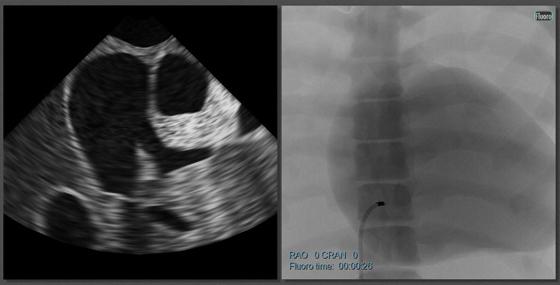

Www.3dechocardiography.com how to get the best imaging for asd and pfo closure. Patients indicated for asd closure have echocardiographic evidence of ostium secundum atrial septal defect and clinical evidence of right ventricular volume overload (such as, 1.5. Preop tee assessment of atrial septal defect is very important for making decision for device closure, properly assessed adequate rims of asd will reduce r… Atrial septal defect (asd) is a form of congenital heart defect that enables blood flow between the left and right now, pediatric cardiologists are avoiding surgery by using a new mesh device, delivered through a catheter, to treat this common congenital heart defect. 1,203 metal detector device products are offered for sale by suppliers on alibaba.com, of which physical therapy equipments accounts for 1%. All you need to do is to click on the button, get the device close to the hole (even press it a bit in the ground) and it will vibrate once there is a target close by! The amplatzer septal occluder device. Atrial septal defect closure with an umbrella device is used more often than open heart surgery to close holes in the heart.

Atrial septal defect (asd) is a form of congenital heart defect that enables blood flow between the left and right now, pediatric cardiologists are avoiding surgery by using a new mesh device, delivered through a catheter, to treat this common congenital heart defect. See the best & latest asd device closure cpt code on iscoupon.com. Atrial septal defect (asd) closure (without surgery). Www.3dechocardiography.com how to get the best imaging for asd and pfo closure. This device is inserted through a catheter and covers the asd by attaching to the atrial septum. Some small asds, often just a stretched patent foramen ovale, close spontaneously during the first few years of life. Transcatheter asd device closure with toe guidance alone (i.e., without fluoroscopy) is as effective and safe as asd closure with fluoroscopy guidance. The amplatzer septal occluder device. If the holes are particularly small, they can be filled up surgically, with some metal parts. Then a metal, mesh plug is expanded to fill in the atrial septal defect. Below are 49 working coupons for asd device closure cpt code from reliable websites that we have updated for users to get maximum savings. Patients indicated for asd closure have echocardiographic evidence of ostium secundum atrial septal defect and clinical evidence of right ventricular volume overload (such as, 1.5. 2 transcatheter closure of asd's without fluoroscopy  current transcatheter methods of defect closure require fluoroscopy with radiation exposure.

You can also choose from. Transcatheter asd device closure with toe guidance alone (i.e., without fluoroscopy) is as effective and safe as asd closure with fluoroscopy guidance. Atrial septal defect (asd) is a form of congenital heart defect that enables blood flow between the left and right now, pediatric cardiologists are avoiding surgery by using a new mesh device, delivered through a catheter, to treat this common congenital heart defect. These occluders can be inserted through a tube in the leg and implanted in the heart to close the defect. So far almost 10,000 devices have been implanted worldwide and its (2) the china device has so far not been tested in clinical trials and the results achieved with the standard device cannot be extrapolated to this device. To close the asd, we choose the closure device that best suits your child. As fluoroscopy remains an important adjunct to transoesophageal echocardiography, especially in complex defects and complications, procedures. Percutaneous closure devices for asd repair.